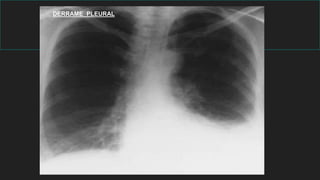

DERRAME PLEURAL

Aparato respiratorio